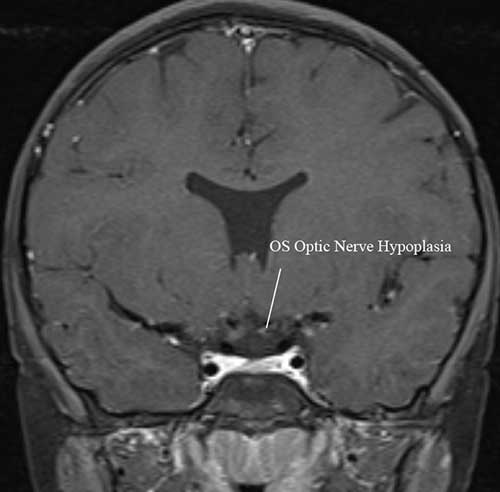

Figure 4: MRI Brain Coronal T1 FS thin post GAD demonstrating left ON hypoplasia (note: this imaging sequence was taken from another patient with ON hypoplasia, absent septum pellucidum, and pituitary hypoplasia). (click image for higher resolution)

MRI Brain, coronal t1 FS think post GAD